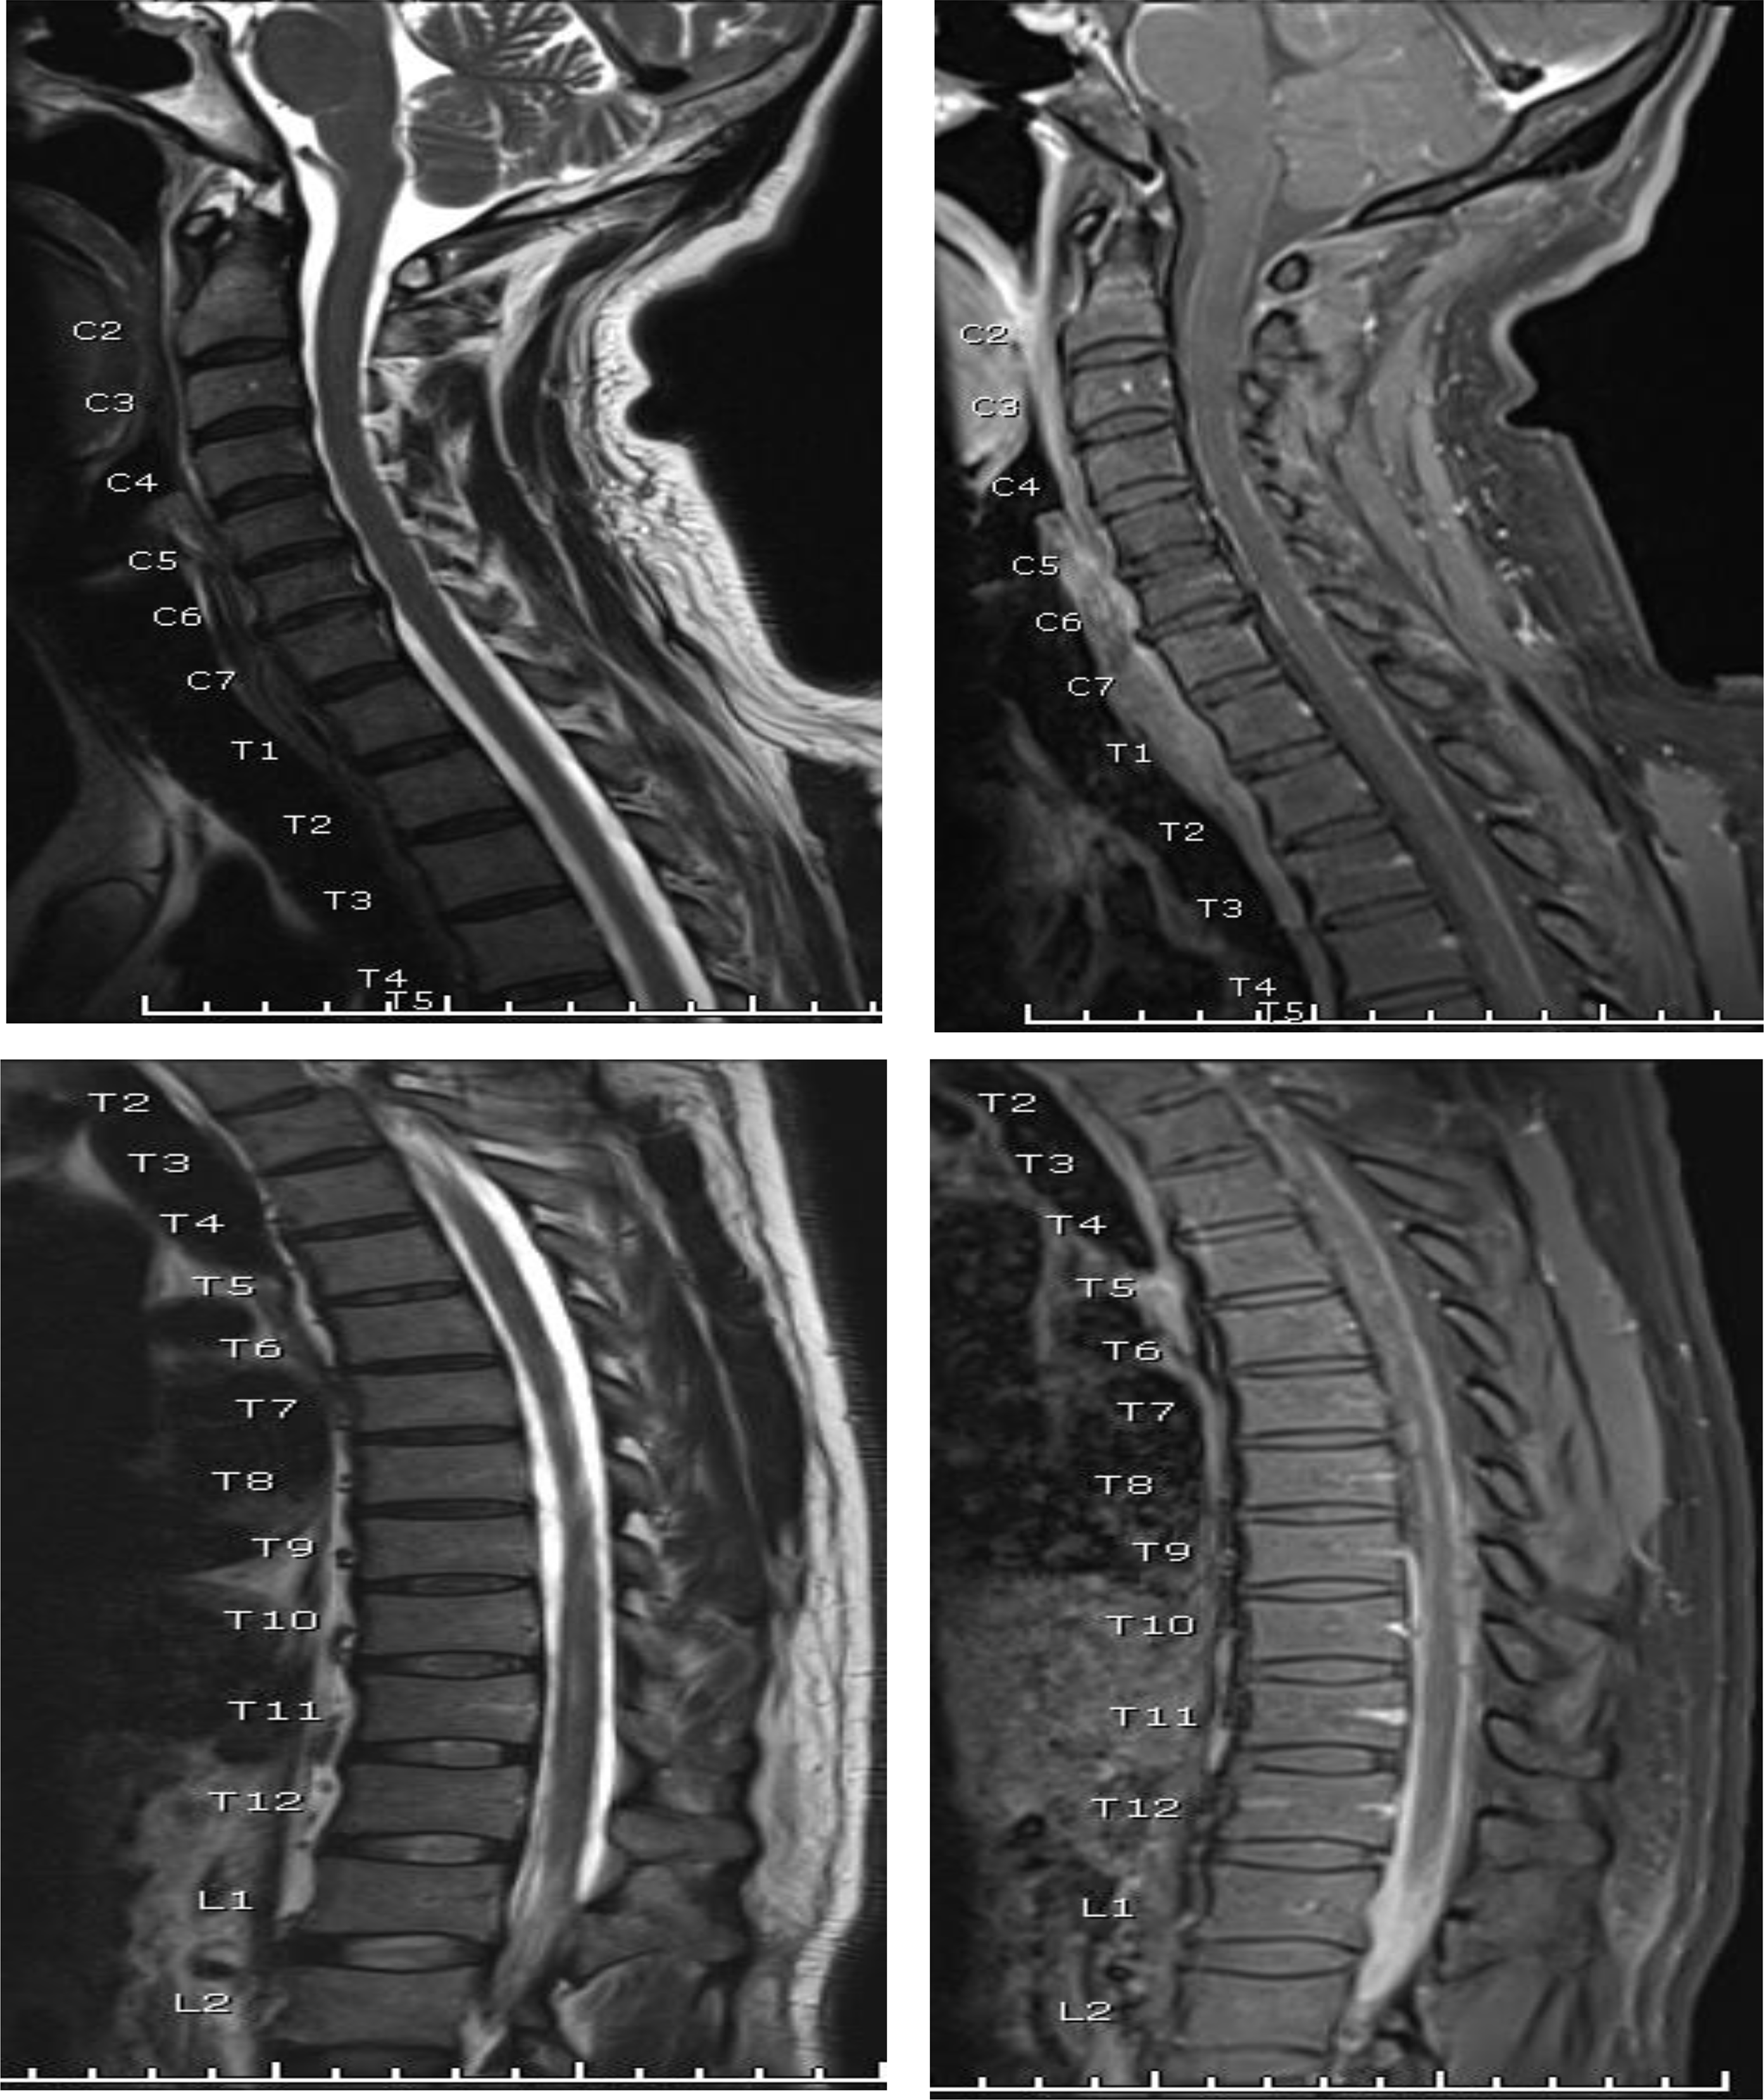

Figure 2. Sagittal T2WI and post-contract T2WI of the whole sping showing evident meningeal thickening and enchancement circumscribing the spinal cord and extending extensively along the cadua equina nerve roots almost completely replacing the CSF spaces and resulting in dry CSF puncutre. © 2021 Abdulrabu, Ebrahim, Warki, Alsotuhy, Anjum, licensee HBKU Press.